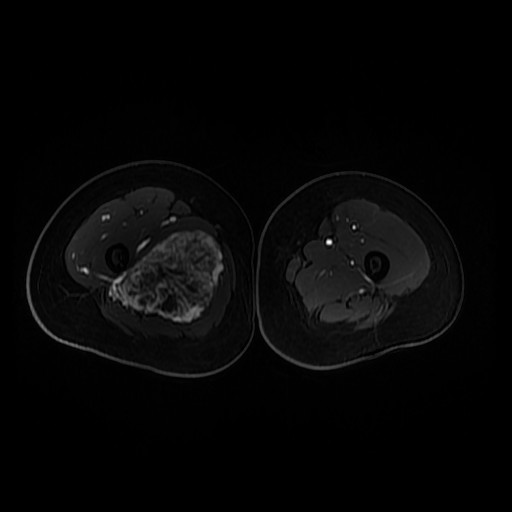

诊断:肺占位性病变(转移瘤?);大腿软组织疾患(右侧大腿肿物) 治疗:入院右下肢MR平扫+增强扫描:右侧大收肌软组织占位性病变,考虑间叶源性恶性肿瘤可能性大,血管源性可能?瘤周多发静脉曲张及侧枝循环形成,建议CT增强扫描进一步检查明确血管情况。遂于声引导下右大腿肿物穿刺活检,病理结果提示:(右大腿肿物)送检穿刺组织,肿瘤细胞形成器官样及腺泡状结构,细胞巢间为纤维性分隔,细胞呈大圆形、多边形,胞质丰富透亮,部分呈嗜伊红色,细胞核大,核分裂象少见,结合临床病史及免疫组化,考虑为腺泡状软组织肉瘤。免疫组化结果(①):CK(-),Vim(-),Ki-67(5%+),HMB45(-),MelanA(-),SMA(+),desmin(-),Myogenin(-),MyoD1(-),S100(-),NSE(部分+),CD56(-)。